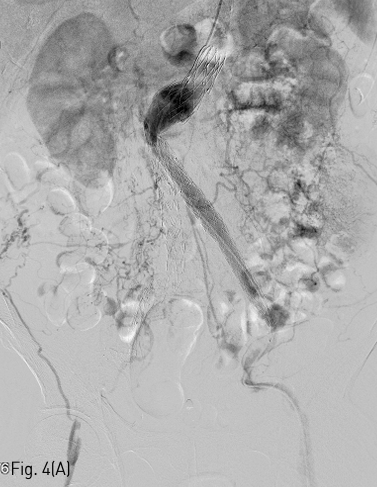

시술전 CT를 면밀히 검토하여 혈전성 폐색부위는 AngioJet (Boston scientific, Boston, US) 기구를 이용하여 개통시킨 다음, 인조혈관의 주체(main body) 부위와 분지 인조혈관사이의 이행대에 생긴 인조혈관 꺽임은 풍선확장식 스텐트를 이용하여 kissing balloon 기술로 설치하기로 계획하였다. 초음파 유도 하에 양측 총대퇴동맥을 천자하고 좌측 경로를 이용하여 5Fr pigtail catheter (COOK medical, Søborg, Denmark) 를 이용하여 혈관조영술을 시행하였다(Fig. 4A).

Fig 4A

(A) Abdominal aortography shows well correlated findings with CT angiography.